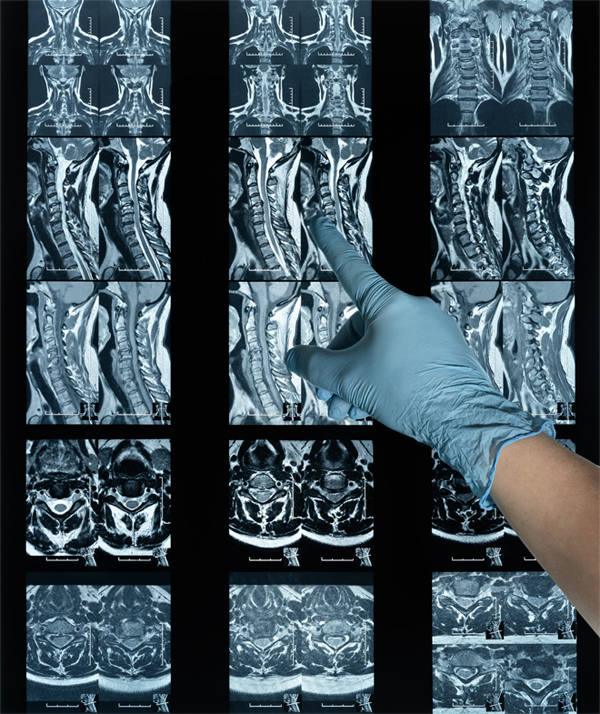

Khi bị thoát vị đĩa đệm, nhân nhầy bên trong phá hủy vòng sợi (bao xơ) và chèn ép rễ thần kinh, gây ra tình trạng đau nhức, tê bì lan dọc theo đường đi của dây thần kinh. Điều này khiến chức năng vận động của người bệnh giảm sút rõ rệt: Khó vận động các chi, không thể gấp - duỗi hay nhấc được các chi, khả năng lao động và sinh hoạt từ đó cũng bị ảnh hưởng nghiêm trọng, thậm chí xuất hiện tình trạng teo cơ chân, tay,… nặng hơn cả đó chính là biến chứng bại liệt vĩnh viễn.

Tình trạng thoát vị đĩa đệm xảy ra là do vòng sợi bao quanh đĩa đệm bị nứt, rách do chấn thương hoặc quá trình thoái hóa. Việc chịu áp lực quá nặng trong thời gian dài làm cho các mô liên kết sợi collagen cấu thành vòng sợi đĩa đệm trở nên lỏng lẻo, mất độ đàn hồi và sự dẻo dai nên dễ bị tổn thương,… khiến cho nhân nhầy bên trong chảy ra, chèn ép lên rễ thần kinh, tủy sống. Hệ quả là gây ra những cơn đau nhức, tê buốt triền miên lan từ cổ xuống tay hoặc từ lưng xuống chân.